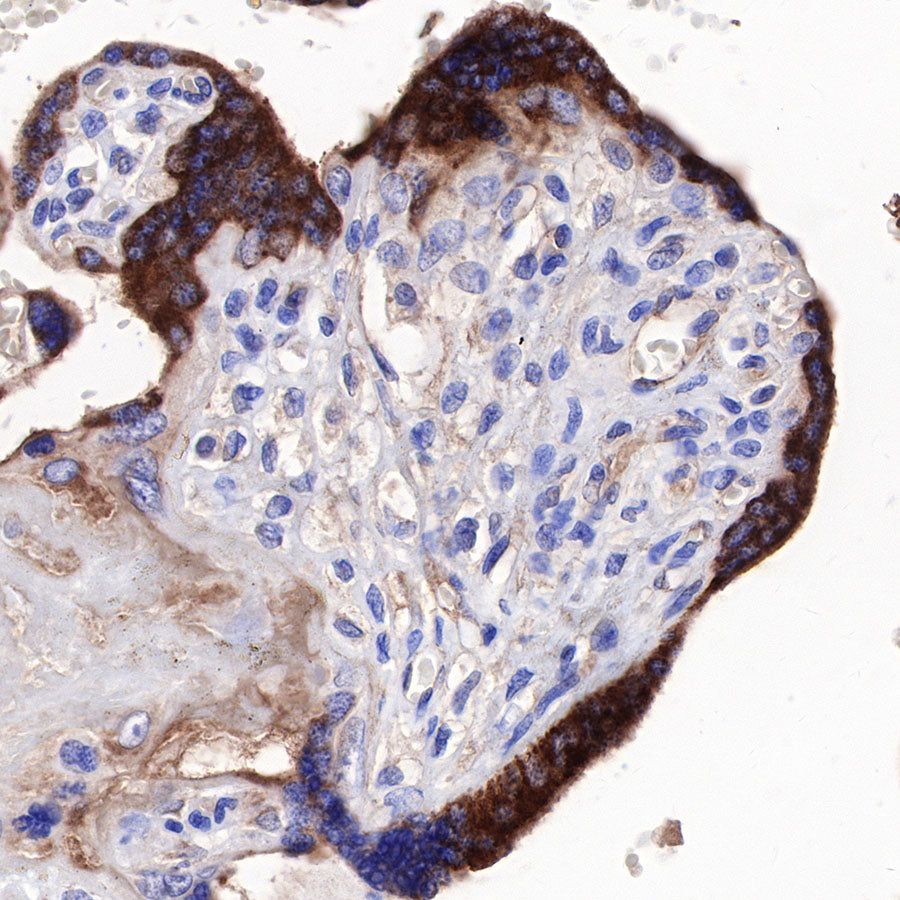

IHC shows positive staining in paraffin-embedded human placenta. Anti-sFlt-1/VEGF Receptor 1 antibody was used at 1/1000 dilution, followed by a HRP Polymer for Mouse & Rabbit IgG (ready to use). Counterstained with hematoxylin. Heat mediated antigen retrieval with Tris/EDTA buffer pH9.0 was performed before commencing with IHC staining protocol.